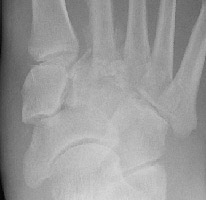

Charcot: AP - Dislocation tarsometatarsal joint

+++

Charcot: AP -

++